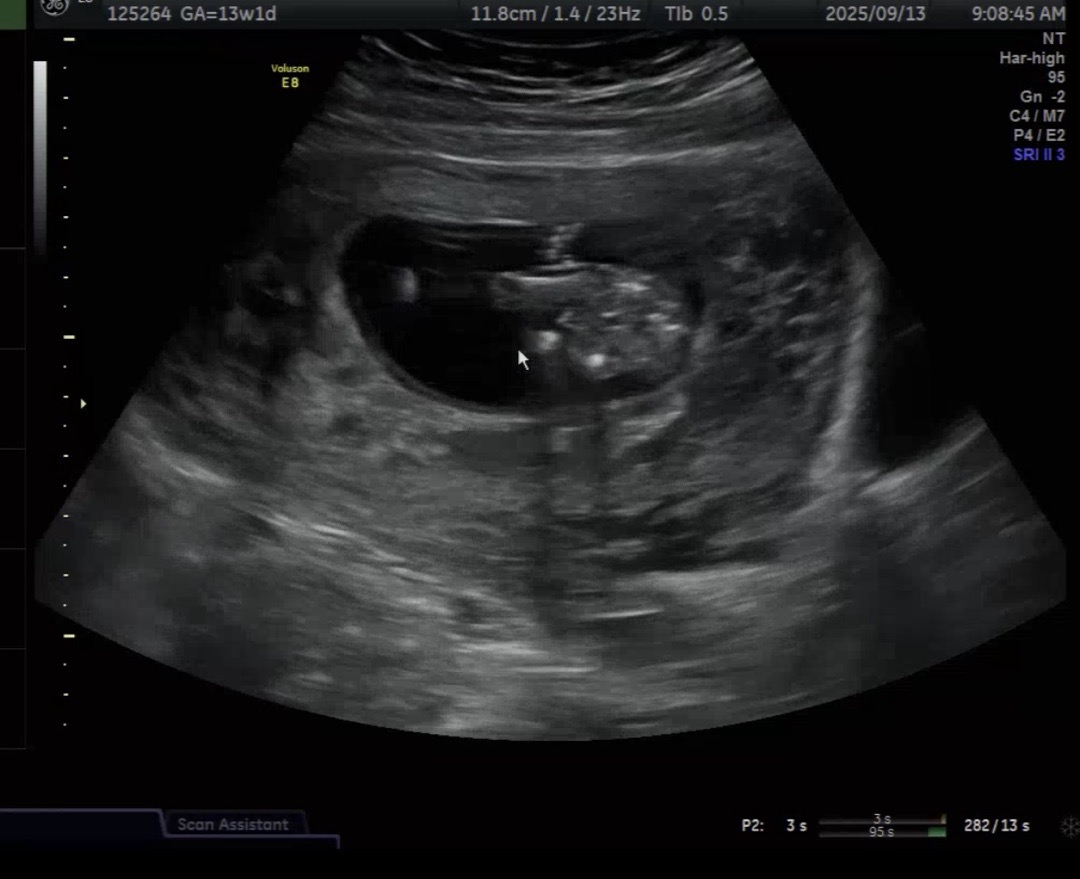

13주 다리사이에 튀어나온거.. 맞나요?

13주1일인데 이시기엔 다 생식기가 튀어나와있나요??

튀어나오긴 하는데 삼각점이네요 아들한표요~